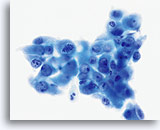

Postpartum

HSIL in a postpartum sample. Note the increased N/C ratio and abnormal chromatin in the HSIL cells as compared to the parabasal cells, apparent even at low magnification.

20X